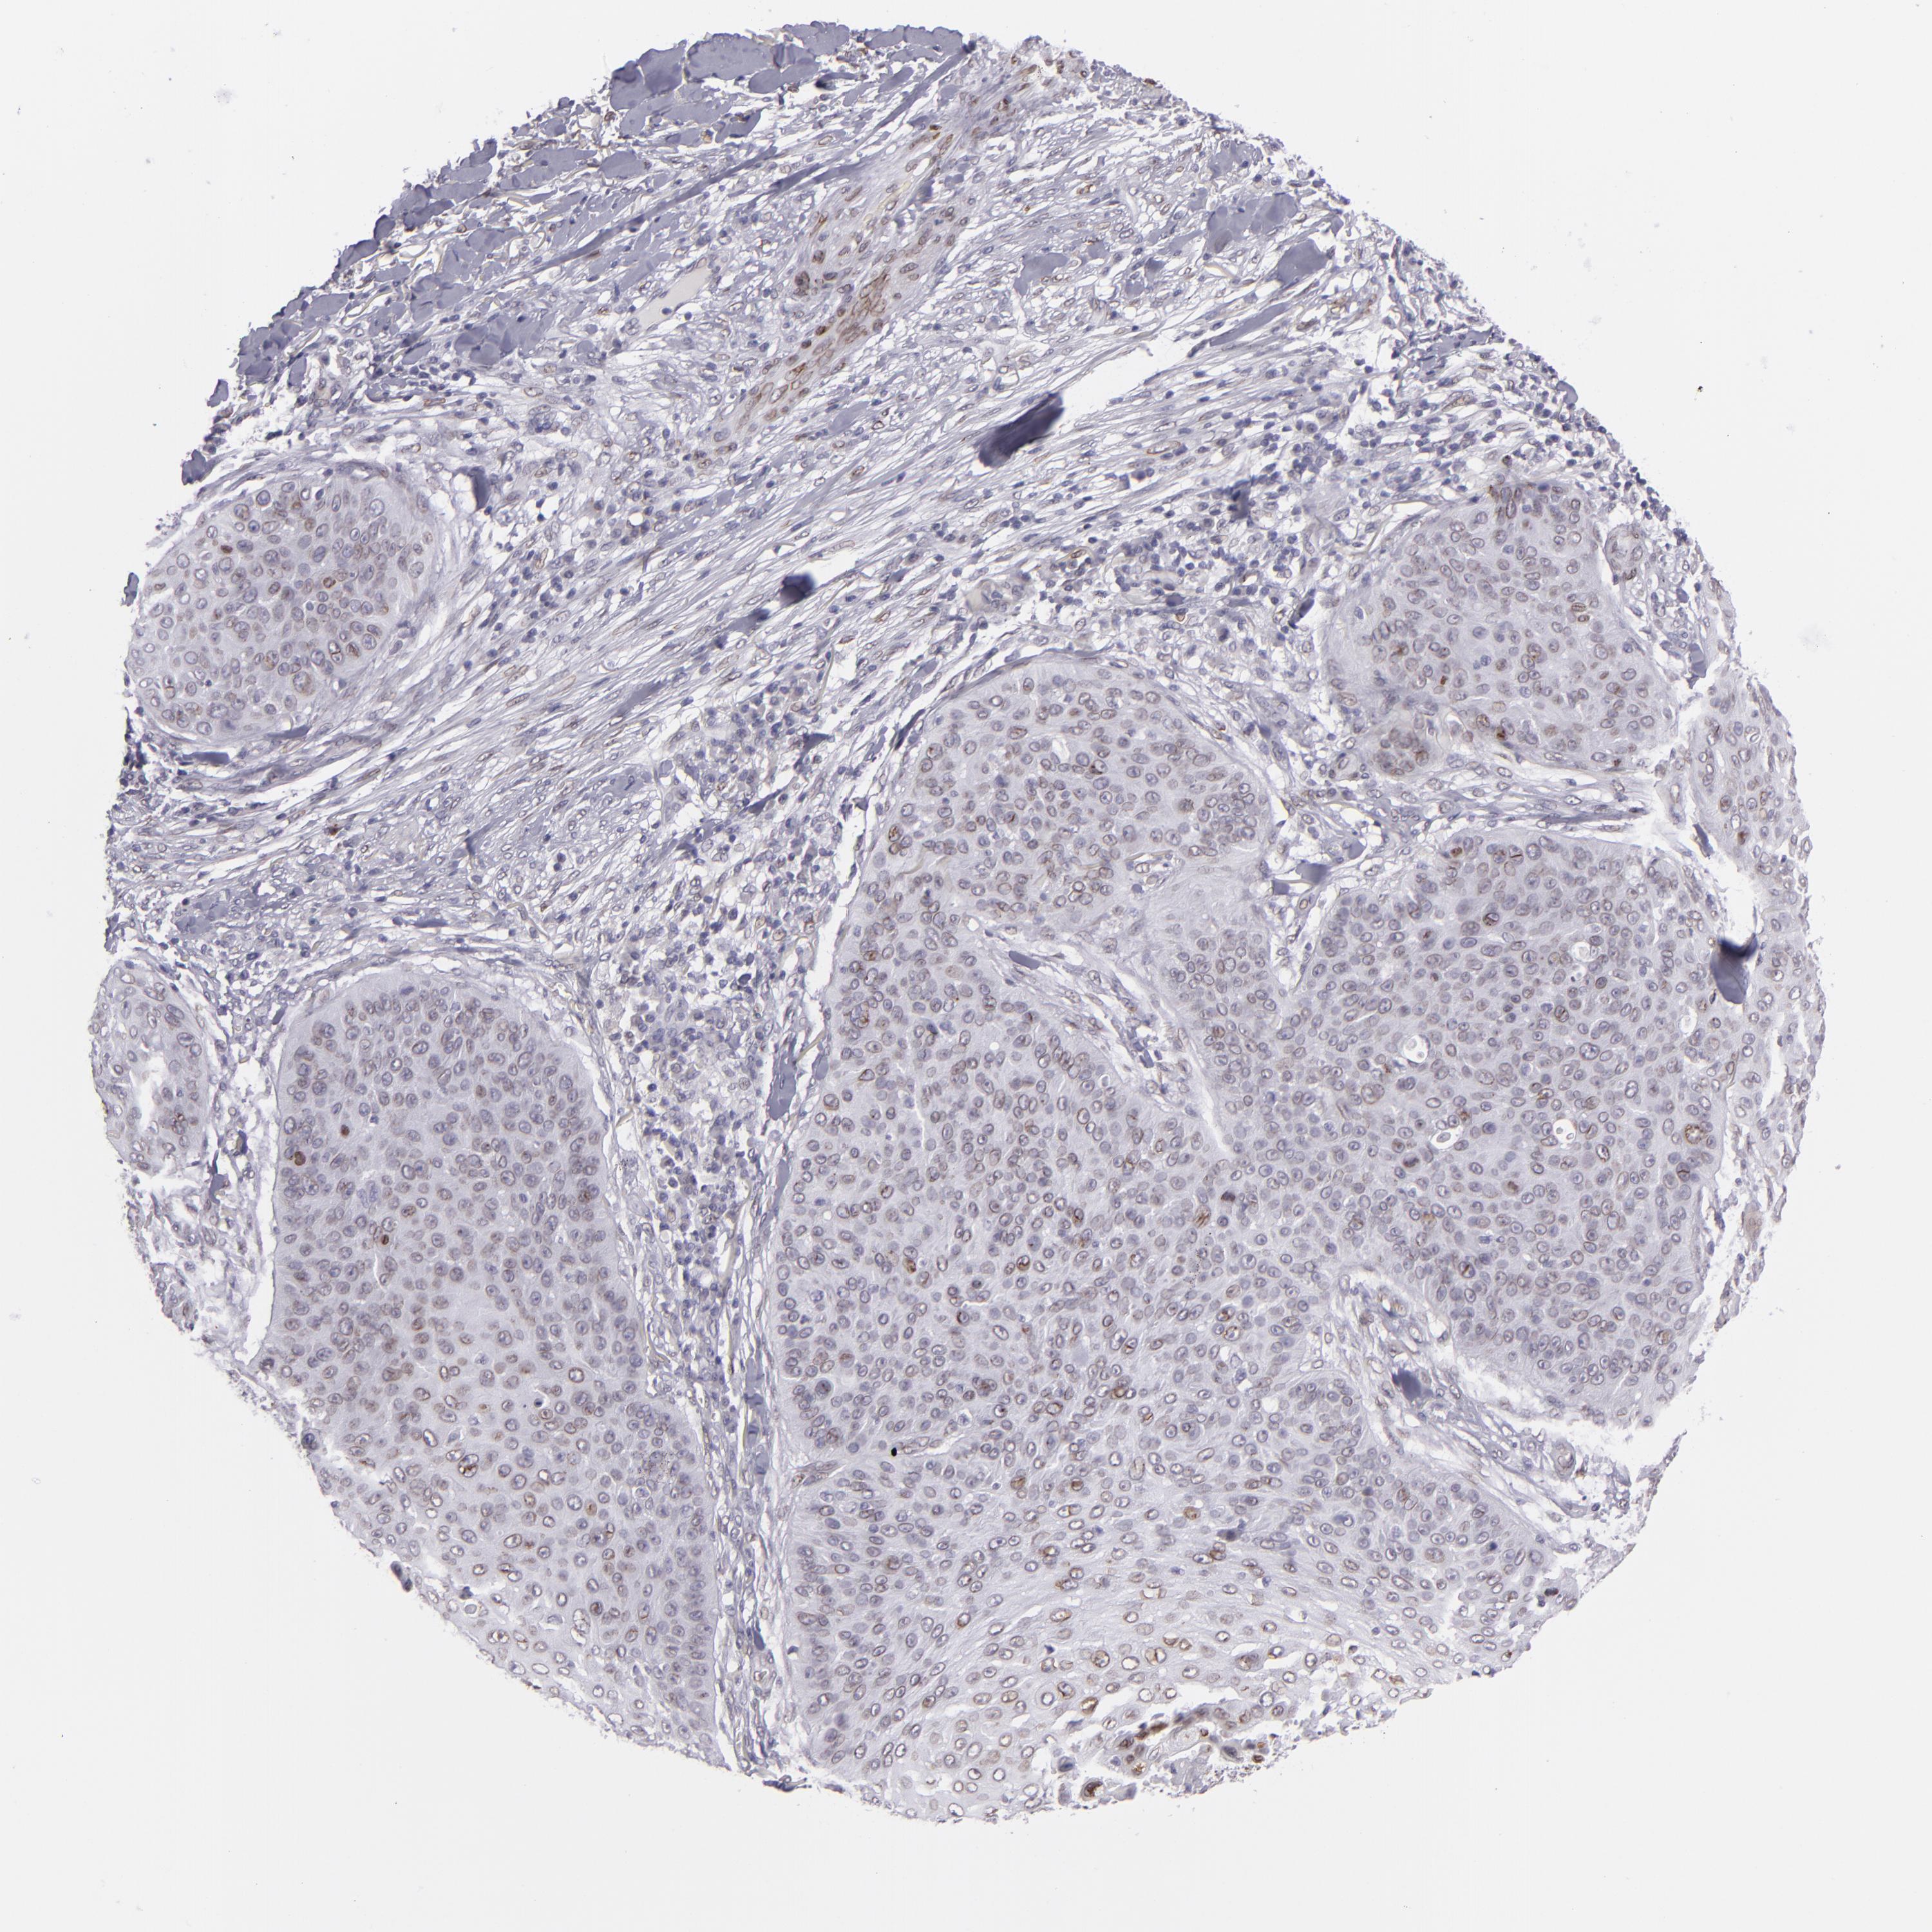

SKIN CANCER - Protein expressioni

A mouse-over function shows sample information and annotation data. Click on an image to view it in a full screen mode. Samples can be filtered based on level of antibody staining by selecting one or several of the following categories: high, medium, low and not detected. The assay and annotation is described here.

Antibody stainingi

Antibody staining in the annotated cell types in the current human tissue is reported as not detected, low, medium, or high, based on conventional immunohistochemistry profiling in selected tissues. This score is based on the combination of the staining intensity and fraction of stained cells.

Each image is clickable and will lead to virtual microscopy that enables deeper exploration of all samples and also displays staining intensity scores, fraction scores and subcellular localization as well as patient and tissue information for each sample.

Staining

High

Medium

Low

Not detected

Intensity

Strong

Moderate

Weak

Negative

Quantity

>75%

75%-25%

<25%

None

Location

Nuclear

Cytoplasmic/membranous

Cytoplasmic/membranous,nuclear

Basal cell carcinoma

Squamous cell carcinoma, NOS